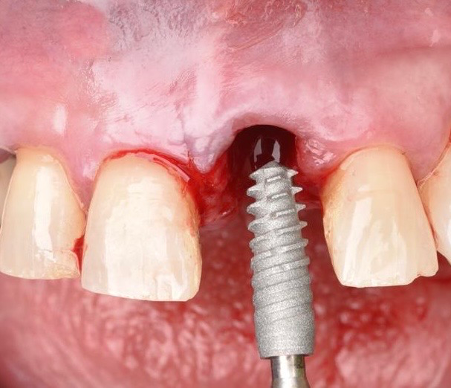

Posteriormente, siguiendo el protocolo de fresado recomendado por el fabricante, se colocó un implante de conexión interna (Klockner Vega Plus®3,6 × 12 mm) (Figura 4), alcanzándose un torque de inserción de 45 N/cm, lo que permitió la realización de una restauración provisional fija inmediata.

El implante se posicionó aproximadamente 4 mm subgingival en sentido vertical y manteniendo un gap vestibular superior a 2 mm en sentido horizontal (Figura 5). Dicho espacio fue rellenado con un xenoinjerto óseo de origen bovino (Bio-Oss®, Geistlich). A continuación, se realizó un injerto de tejido conectivo, obtenido de la tuberosidad maxilar, mediante una técnica de túnel en la zona vestibular, fijándolo con sutura reabsorbible incolora 5/0 (Monocryl Plus, Ethicon®) (Figura 6).